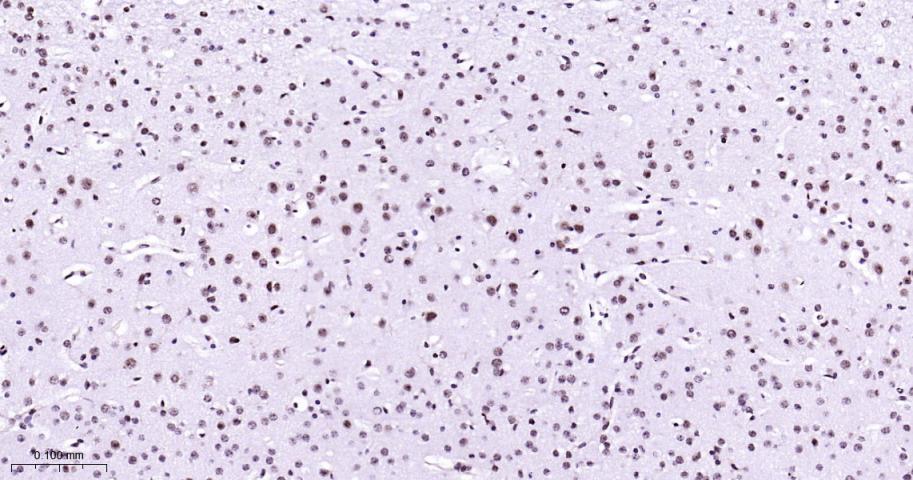

Paraformaldehyde-fixed, paraffin embedded Human Cerebrum; Antigen retrieval by boiling in sodium citrate buffer (pH6.0) for 15 min; Antibody incubation with p38 MAPK Monoclonal Antibody, Unconjugated(bsm-63072R) at 1:200 overnight at 4°C, followed by conjugation to the bs-0295G-HRP and DAB (C-0010) staining.

Paraformaldehyde-fixed, paraffin embedded Rat Cerebrum; Antigen retrieval by boiling in sodium citrate buffer (pH6.0) for 15 min; Antibody incubation with p38 MAPK Monoclonal Antibody, Unconjugated(bsm-63072R) at 1:200 overnight at 4°C, followed by conjugation to the bs-0295G-HRP and DAB (C-0010) staining.

Paraformaldehyde-fixed, paraffin embedded Mouse Cerebrum; Antigen retrieval by boiling in sodium citrate buffer (pH6.0) for 15 min; Antibody incubation with p38 MAPK Monoclonal Antibody, Unconjugated(bsm-63072R) at 1:200 overnight at 4°C, followed by conjugation to the bs-0295G-HRP and DAB (C-0010) staining.